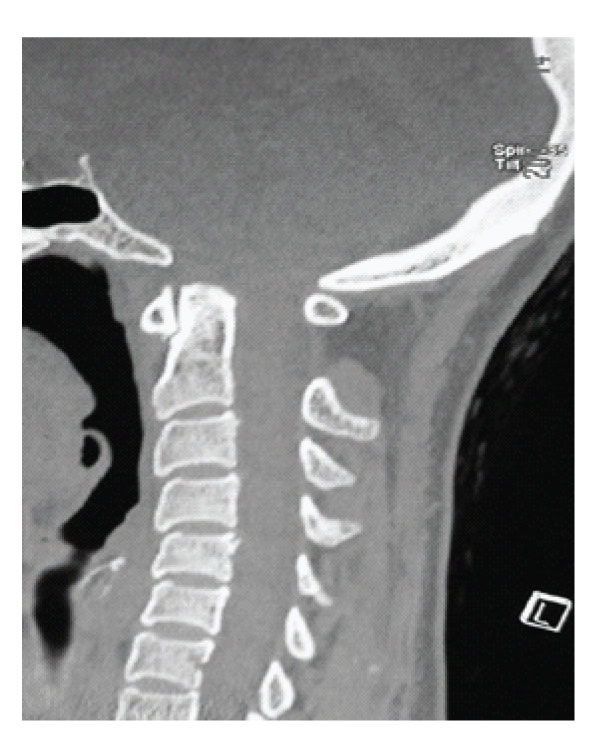

A 45 years old woman was admitted to the hospital with a history of progressive weakness and numbness of the upper extremities. She also had a headache worsening with coughing and gait disturbance. Neurological examination revealed spasticity and weakness of extremities with hyperreflexia. Paresthesia, decreased pain and temperature sensation under C3 level were also observed. Lateral X-rays showed bony abnormality at the craniovertebral junction without basilar invagination. Dynamic

X-ray examination disclosed no instability. Axial CT scans, three dimensional reconstructed CT scans and MRI showed anterior occipitalization of atlas, asymmetrical condyles with hypoplasia of left posterior part of the atlas, rightward deviation of odontoid process and C1-5 syringomyelia without tonsillar herniation [Figure- 1,2,3,4]. Posterior part of the axis was also asymmetrical. There was no appearance of basilar invagination although the tip of the axis was 2 mm superior to the foramen magnum level (McRae line).

Antero-posterior diameter of foramen magnum was 20 mm; no bony compression to neural structures including odontoid process was detected, however anterior subarachnoid space could not be seen at the level of brain stem. MR angiography disclosed aplasia of left vertebral artery with a nearly normal trace of the right vertebral artery. The patient was treated by a posterior fossa decompression. In the operation, suboccipital craniectomy was performed. The right lamina of the atlas was also removed. Dural surface became expanded and pulsatile suggesting foramen magnum stenosis. CSF flow was observed after opening the dura mater. A large duraplasty was made with dural graft to maintain the CSF flow. Following the decompression and large duraplasty, occipital cervical fusion using C2 laminar screwing was performed. Post-operative period was uneventful, spasticity and weakness of the extremities and hyperreflexia improved. MR examination obtained six months after the operation showed the resolution of the syringomyelia [Figure 3,4].